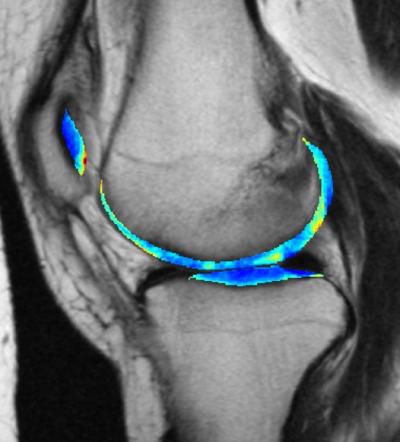

image: The cartilage in this MRI scan of a knee is colorized to show greater contrast between shades of gray.

Kundu et al. (2020) PNAS